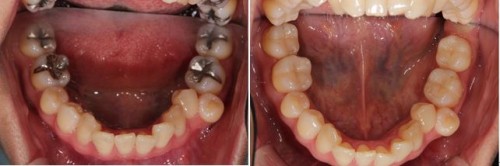

術前術後です。奥歯2本をオールセラミックインレーで治療しました。手前の銀歯はダイレクトボンディングを行いました。

セラミックインレー

費用11万円

リスクとして歯を削る量が多いため痛みが出る可能性と強い力によって割れる可能性がある。

ダイレクトボンディング

費用5万円

リスクとして欠ける可能性がある(修復可能)。